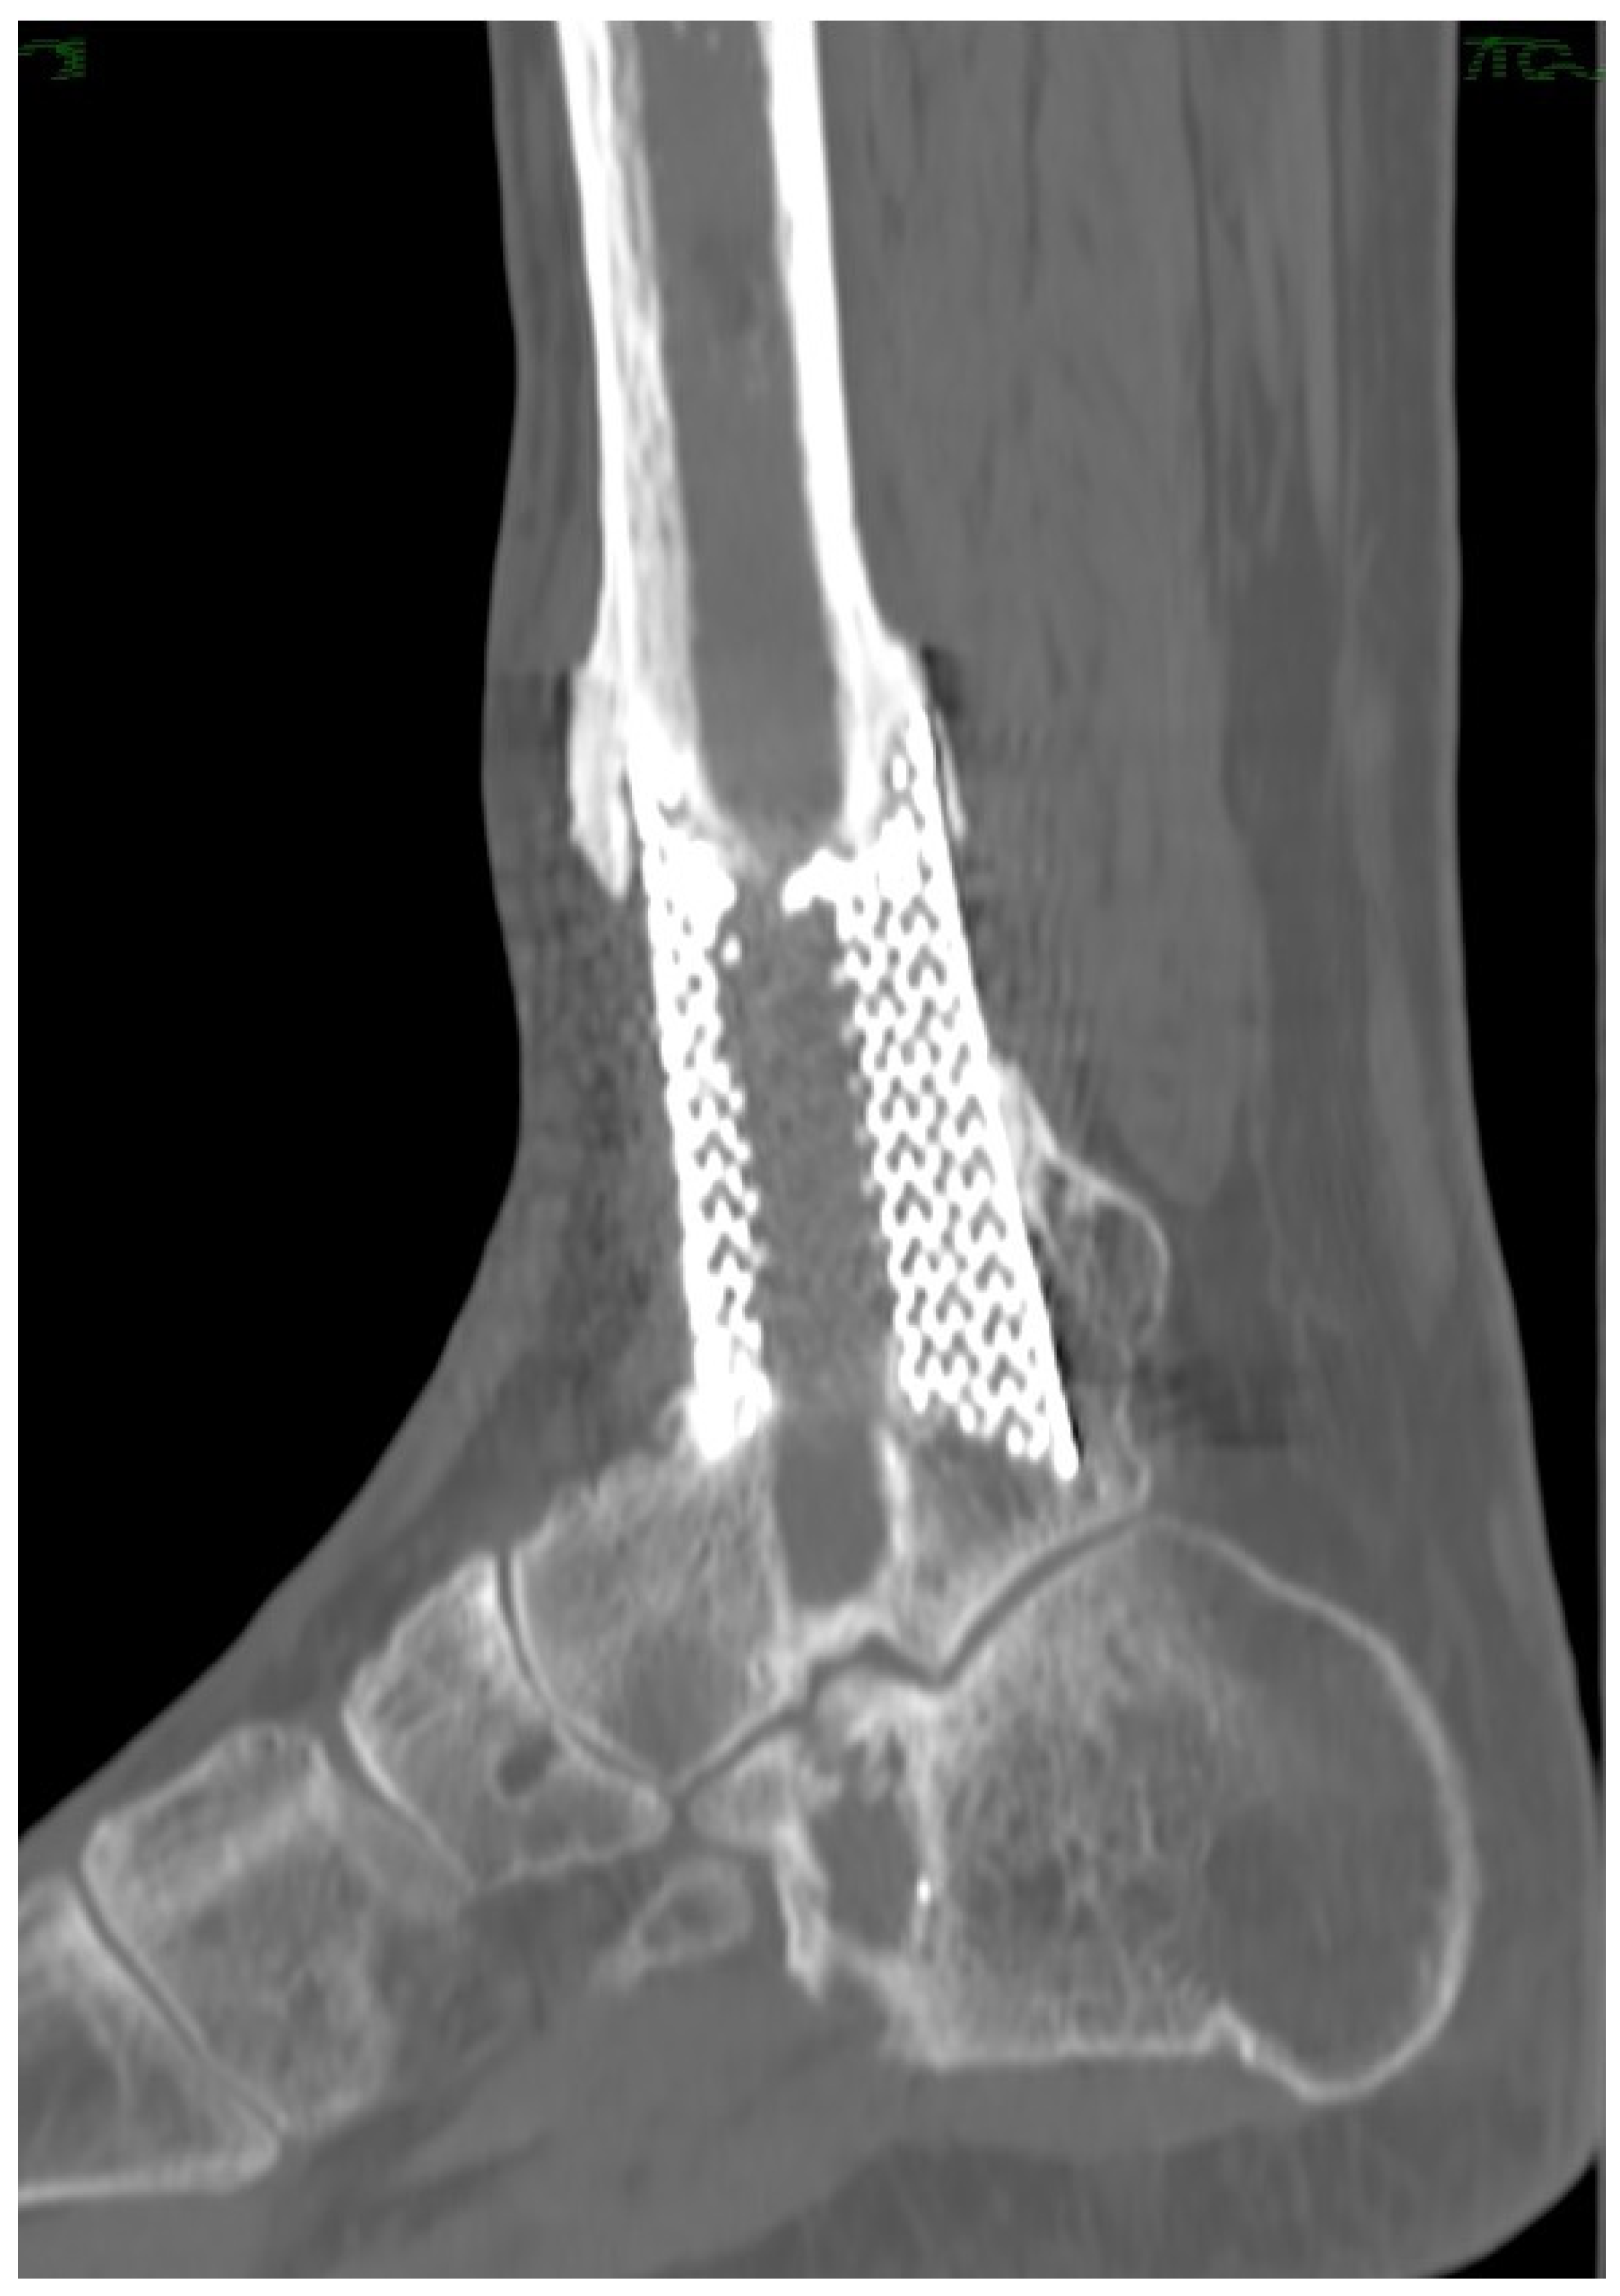

Custom-Made Implants in Ankle Bone Loss: A Retrospective Assessment of Reconstruction/Arthrodesis in Sequelae of Septic Non-Union of the Tibial Pilon

2. Materials and Methods

2.1. Planning Procedures and 3D Technology

2.2. Study Population

3. Results